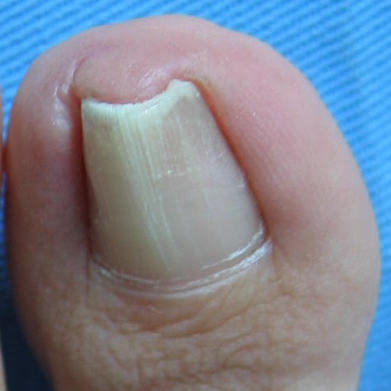

Exóstosis subungueal

Exóstosis subungueal: antes Exóstosis subungueal: después